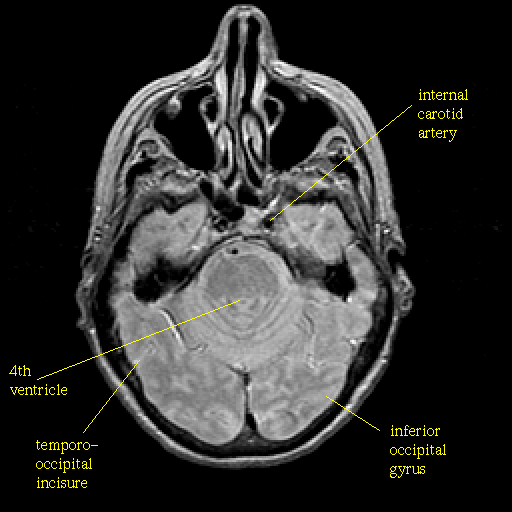

Proton density-weighted structural MR: Slice 16

Slice 16